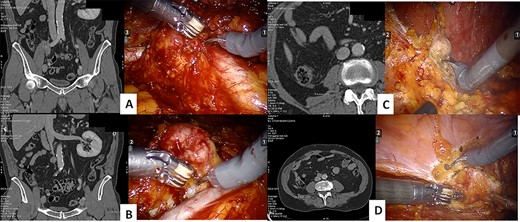

The procedure started with the excision of the right common iliac lymph nodes and then moving to the iliac bifurcation lymph nodes. The surgery continued with the access to the interaortocaval space, with the excision of a 4 cm mass where the IVC was carefully defined with meticulous dissection to prevent inadvertent violation (Fig. 1). At last, the procedure continued with the excision of retroperitoneal fat of the right renal fossa and of a 2 cm peritoneal nodal recurrence.

CT scan and intraoperative image of the: iliac bifurcation lymph node recurrence (A), the interaortocaval space lymph node recurrence (B), the renal fossa recurrence (C) and the peritoneal recurrence (D)